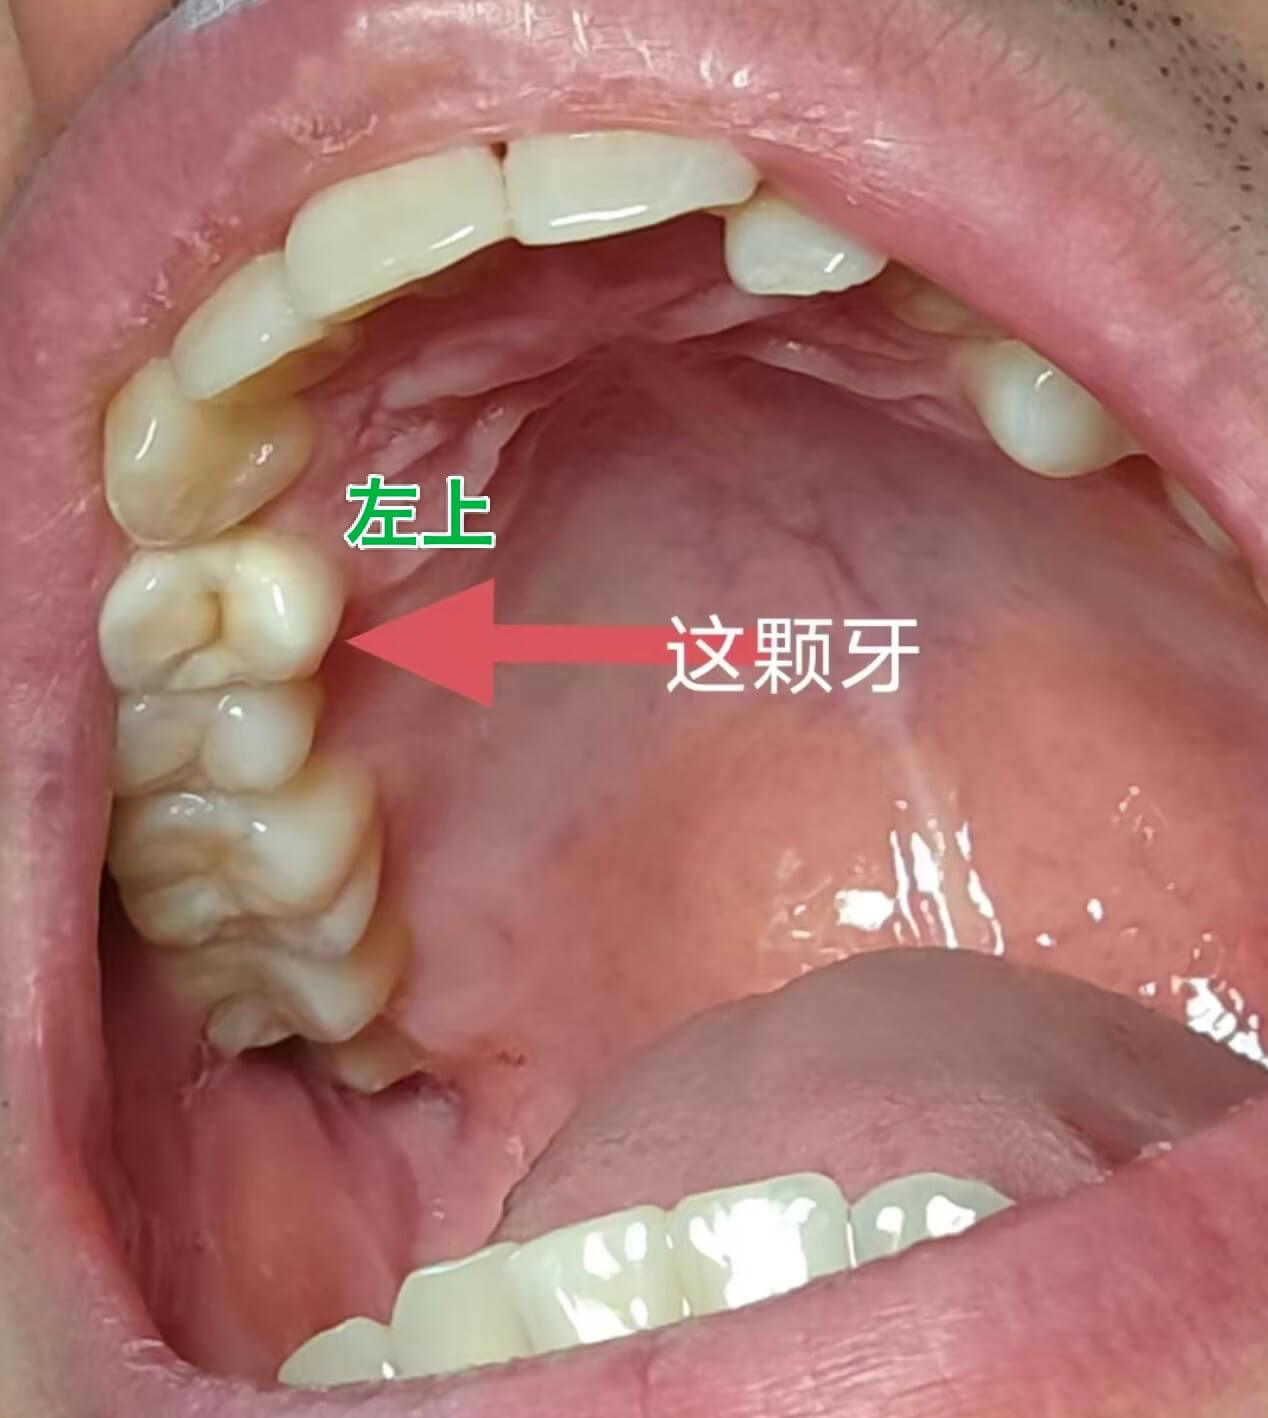

我长期夜磨牙(超过 10 年),每晚磨牙声都很大。最近两年,开始感觉左侧牙齿咬合不舒服,特别是左上第四颗牙(从门牙往左数第四颗),放松时上下牙咬不齐,吃酸甜东西也变得敏感。我怀疑是常年磨牙,把这颗牙磨得凹陷,导致咬合关系出了问题。 今年 4~5 月开始,口腔两侧有了“颊白线”如下图 3 示例。

我感觉左上这颗牙像个“柱子”,被磨低了,导致整个左侧咬合都低了,脸也感觉有点往左偏。我猜测这可能是咬合创伤导致的咬合不舒服、有“颊白线”。

我去看了两家诊所,医生都建议我做正畸。他们用咬合纸检查后说我左上这颗牙先接触,还建议打磨一点。但我很纳闷,本身它就磨损了,再磨不是更凹陷了吗?我感觉应该把磨损的部分补回来 or 做牙冠,恢复牙齿高度,而不是去改变整个牙列。 但医生的主观视角里,是我这颗牙一直这样、一直先接触,也不给我做相关的更具体的咬合检查。即便我要求他们也觉得没必要。

- 如果我的问题确实是咬合不稳或咬合高度降低, 我能否先通过嵌体或牙冠来恢复这颗牙齿的高度,再考虑其他治疗?

另外我没看错的话,你好像还有颗阻生智齿,这个看上去是要去拔掉的,要小心前面那颗大牙。